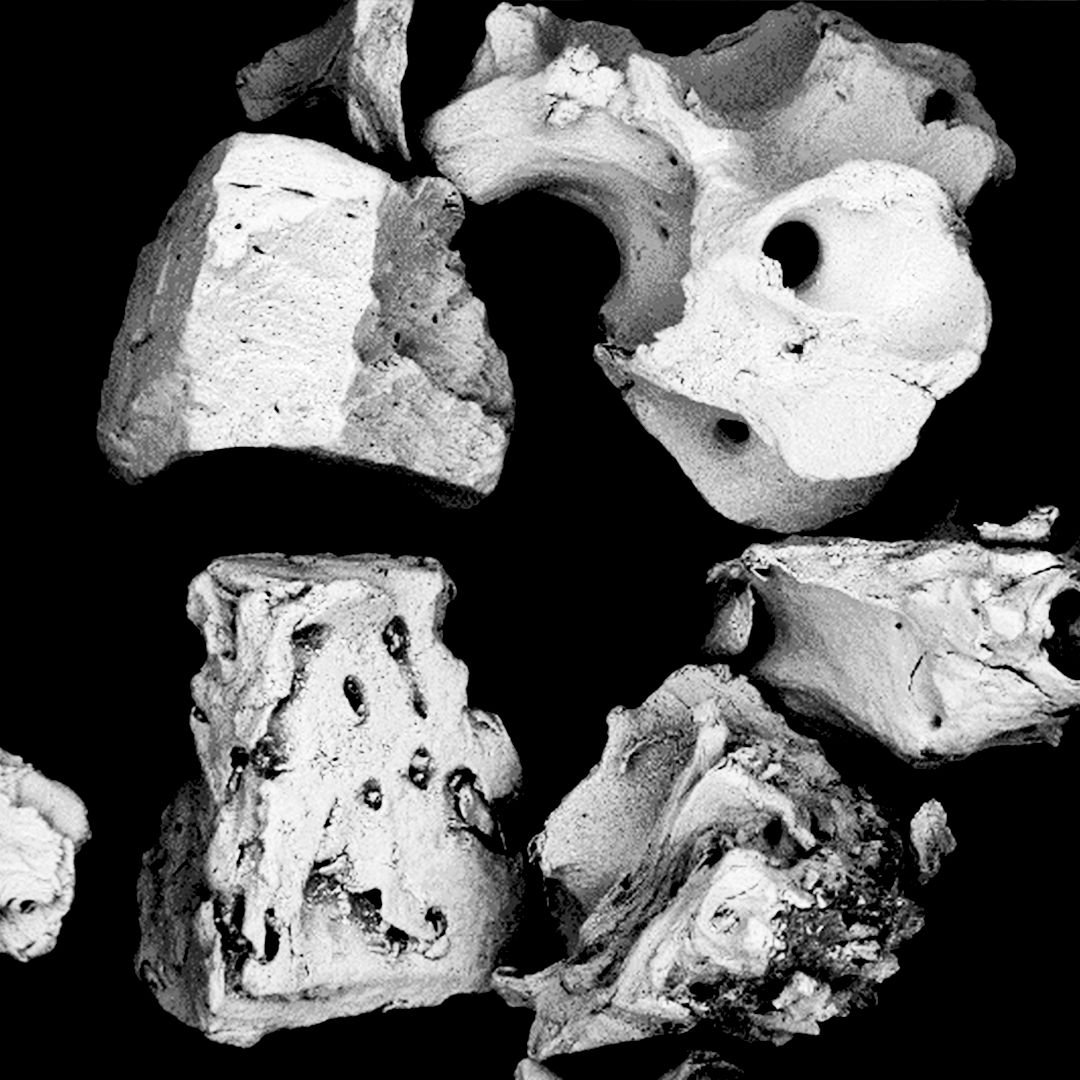

Análisis topográfico.

La microestructura del injerto óseo Bonefill® , analizada mediante SEM/EDS, reveló que el producto presenta una estructura típica del hueso cortical y esponjoso humano, con poros interconectados, y que, tras el proceso fisicoquímico al que se somete la materia prima para su fabricación, conserva la estructura característica de este tipo de tejido. La presencia de poros y el mantenimiento de la estructura cristalina trabecular del hueso son factores fundamentales para el éxito de los fenómenos celulares de deposición de células osteoprogenitoras sobre el injerto, su reabsorción y la formación de nuevo hueso en su lugar.